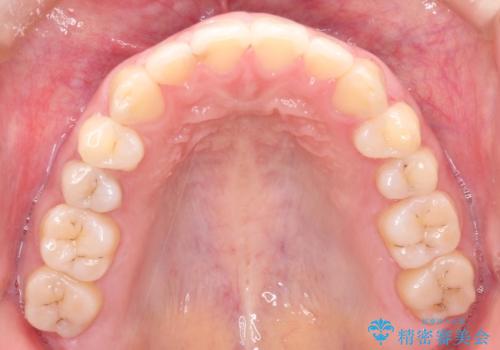

上下の前歯が当たらない インビザラインによる開咬の矯正治療

- 上下の前歯の間に隙間があるとのことで来院されました。

開咬とよばれる、奥歯しか上下の歯が接触していない状態でした。

インビザラインにて矯正治療を行うこととなりました。